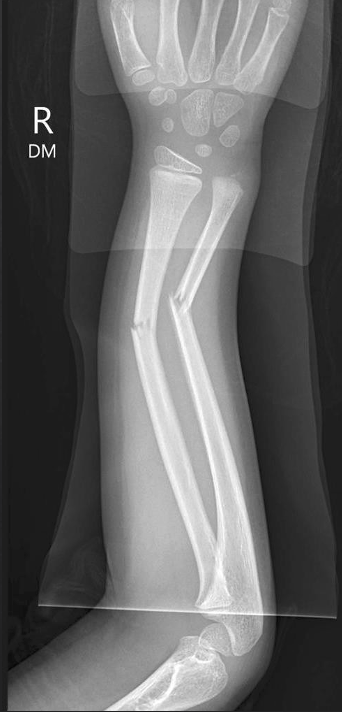

Q

in the shown radiograph

1- what type of fracture

2- site of fracture

3- describe anything else you can see

A

Greenstick fracture of the radial mid-diaphysis and a complete transverse fracture of the mid-diaphysis of the ulna, both associated with angulation